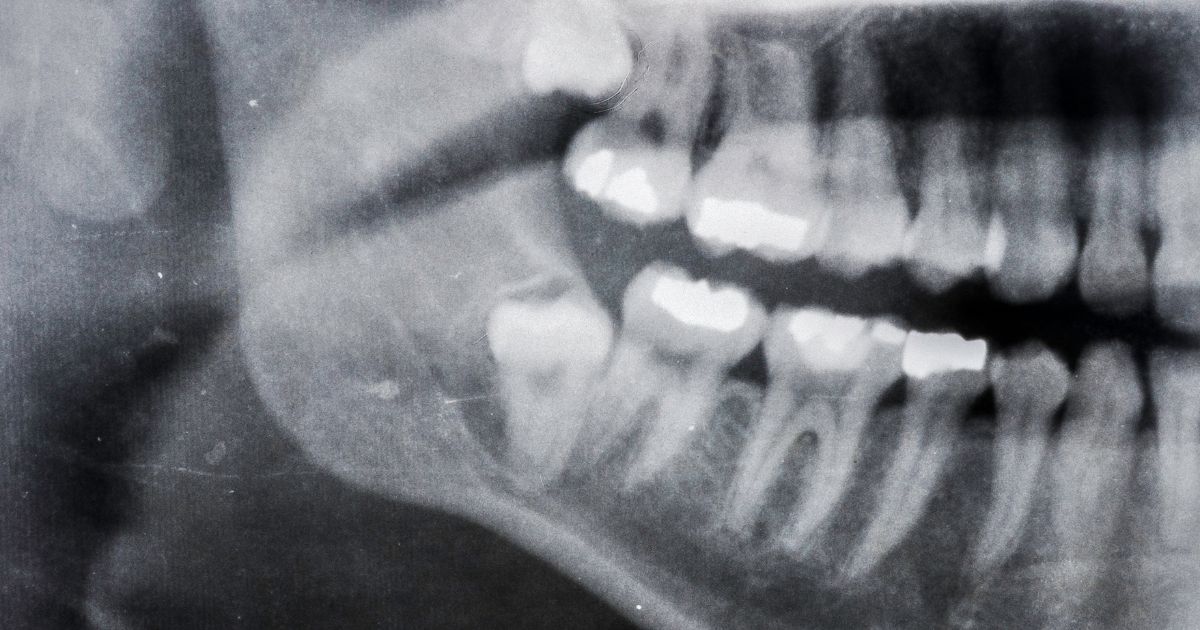

Es importante destacar que no todas las personas experimentan síntomas con un diente retenido, y en algunos casos, puede pasar desapercibido hasta que se detecta en una radiografía dental de rutina. Sin embargo, si experimentas cualquiera de estos síntomas o tienes preocupaciones acerca de un posible diente retenido, es importante consultar a un profesional de la salud dental. Una evaluación dental adecuada ayudará a determinar si es necesario algún tratamiento para abordar la situación. La detección temprana y la atención adecuada son fundamentales para prevenir complicaciones y problemas futuros en la salud bucal.